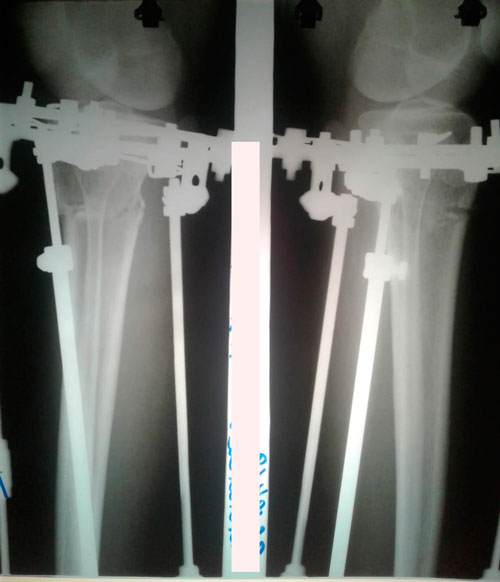

Пациентка - 30 лет.

Дата операции - 04.04.2019г.

Дата снятия аппаратов - 02.07.2019г.

Срок сращения - 89 дней.